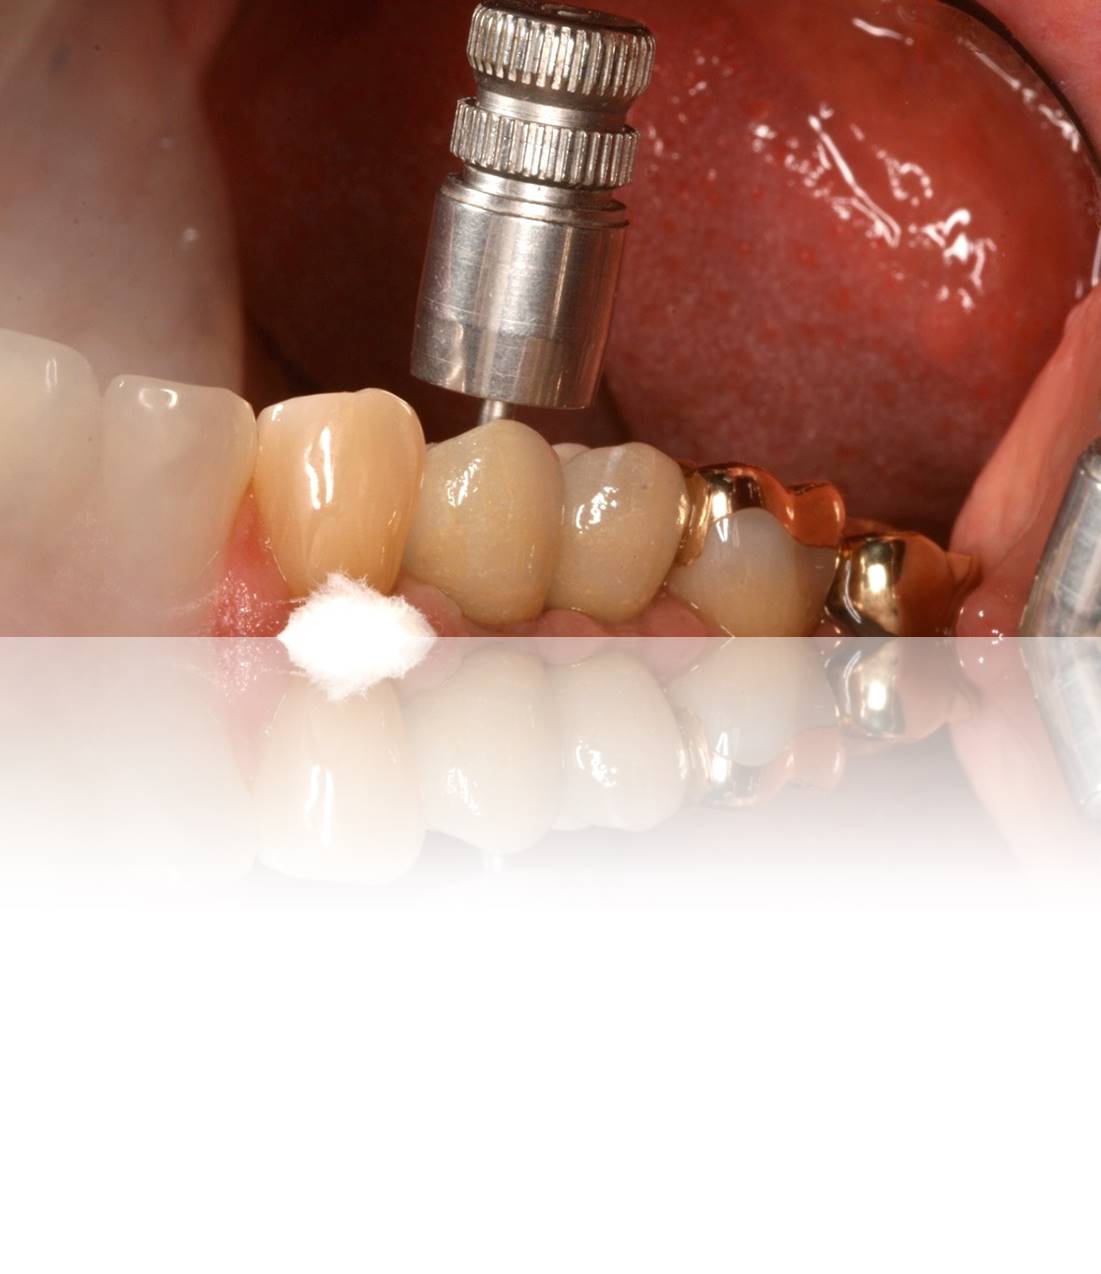

Figure 14. Close-up postoperative view following cementation of the restoration onto the custom-made abutment from Figure 10 through Figure 13.

Figure 14

Then, when placing the abutment/crown in the mouth, complications can be avoided by aligning the abutment to ensure the restoration does not dislodge. The restoration can be lightly primed by coating the internal aspect. When applying cement, note that due to the manner in which restorations are fabricated against implant abutments today, minimal cement is required to achieve retention (Figure 14 and Figure 15).18